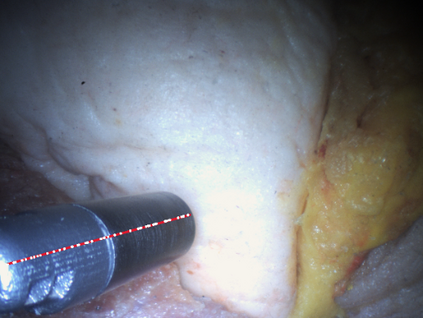

In surgical oncology, it is challenging for surgeons to identify lymph nodes and completely resect cancer even with pre-operative imaging systems like PET and CT, because of the lack of reliable intraoperative visualization tools. Endoscopic radio-guided cancer detection and resection has recently been evaluated whereby a novel tethered laparoscopic gamma detector is used to localize a preoperatively injected radiotracer. This can both enhance the endoscopic imaging and complement preoperative nuclear imaging data. However, gamma activity visualization is challenging to present to the operator because the probe is non-imaging and it does not visibly indicate the activity origination on the tissue surface. Initial failed attempts used segmentation or geometric methods, but led to the discovery that it could be resolved by leveraging high-dimensional image features and probe position information. To demonstrate the effectiveness of this solution, we designed and implemented a simple regression network that successfully addressed the problem. To further validate the proposed solution, we acquired and publicly released two datasets captured using a custom-designed, portable stereo laparoscope system. Through intensive experimentation, we demonstrated that our method can successfully and effectively detect the sensing area, establishing a new performance benchmark. Code and data are available at https://github.com/br0202/Sensing_area_detection.git